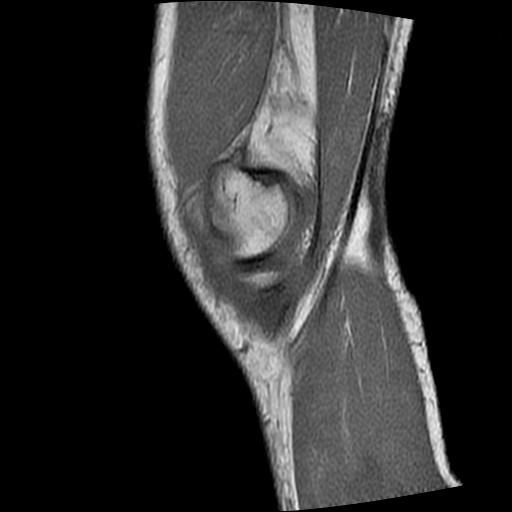

40岁男性,右膝关节外伤,x光平片示,髁间隆突撕脱骨折。

1、前交叉韧带撕裂;

2、外侧半月板后角撕裂;

3、关节腔积液。

前交叉韧带撕裂,关节腔积液.

半月板1-2级损伤   前交叉韧带撕裂伤   关节腔少量积液  诸骨未见新鲜外伤性改变

髁间隆突撕脱骨折;内侧副韧带损伤。

内侧副韧带撕裂及关节腔积液是肯定的,但是前交叉撕裂确定吗?会不会有容积效应的因素,因为前一张前交叉显示清楚,连续性良好,且较光滑。请问楼主有关节镜支持吗?我们医院也经常有这样的患者,但苦于没有关节镜,而无法对照、证实(除非完全断裂),出现了不同的诊断结果只能毫无意义的争论。

1、前交叉韧、内侧副韧带撕裂;

3、关节腔积液。4、髁间脊撕脱骨折。